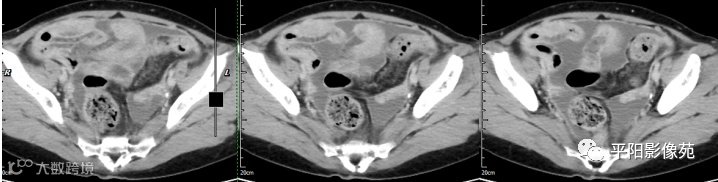

腹部增强 动脉期

腹部增强 门脉期

腹部增强 延迟期

壁腹膜增厚伴或不伴腹水;增厚的腹膜光滑、均匀,呈线带状,部分可见腹膜结节,网膜及肠系膜广泛浸润性改变;增强扫描明显强化。

合并淋巴结肿大,可钙化,若中心干酪样坏死,增强扫描环形强化

湿型:渗出性高密度腹水(CT值20-45HU),高密度由于高蛋白和细胞含量多可能。